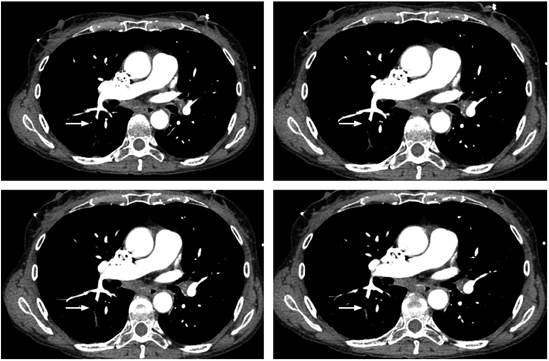

Se tomó una ecografía FAST que descartó taponamiento cardíaco, pero evidenció múltiples burbujas de aire en la vena cava; se trasladó inmediatamente a angiografía por TAC (bajo sospecha de embolia aérea), que mostró aire en la vena cava intrahepática (Figura 2) y émbolo aéreo en una de las arterias pulmonares subsegmentarias del segmento apical del lóbulo inferior derecho (Figura 3). Se trasladó a la paciente a la unidad de cuidados intensivos (UCI), se tomó ecocardiograma transtorácico que mostró colapso de la cava inferior, hallazgo esperado en un estado posreanimación, sin disfunción ventricular izquierda. La paciente evolucionó hacia la mejoría, se extubó al segundo día y se dio de alta a los 4 días sin complicaciones adicionales ni secuelas.

El diagnóstico de esta entidad se dificulta ya que el aire puede ser rápidamente absorbido de la circulación mientras se están realizando los exámenes diagnósticos. El ecocardiograma transtorácico o transesofágico se ha empleado para identificar la presencia de aire en el ventrículo derecho, con dilatación de este, e hipertensión de la arteria pulmonar; y permite descartar anomalías de la contractilidad cardíaca 1,7. La angiografía por TAC puede detectar con mayor sensibilidad un émbolo aéreo 2,6.

En el caso presentado se realizó una ecografía FAST que demostró aire en la vena cava, lo que, junto con el cuadro clínico, sugirió el diagnóstico de una embolia aérea, que fue confirmada con una angiografía por TAC realizada inmediatamente después de la fase inicial de la reanimación cardiorrespiratoria.